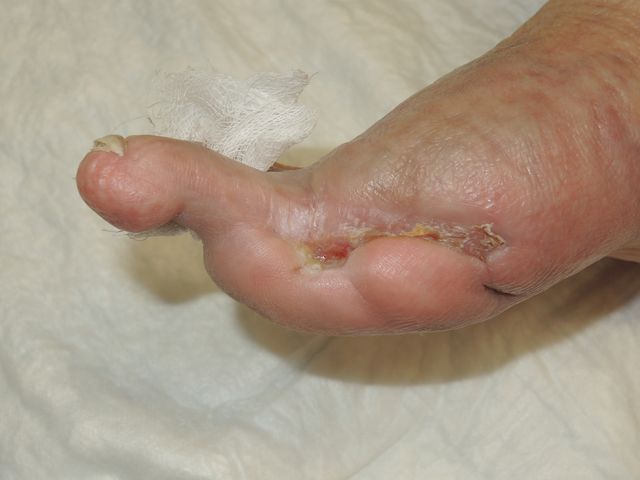

Mal perforante plantar en pie diabético

Mal perforante plantar. Pie diabético.